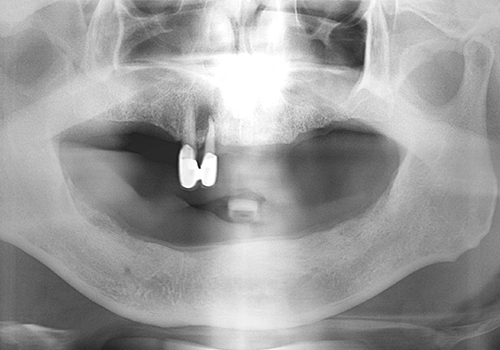

김○근님 임플란트 식립 전

2023년 2월